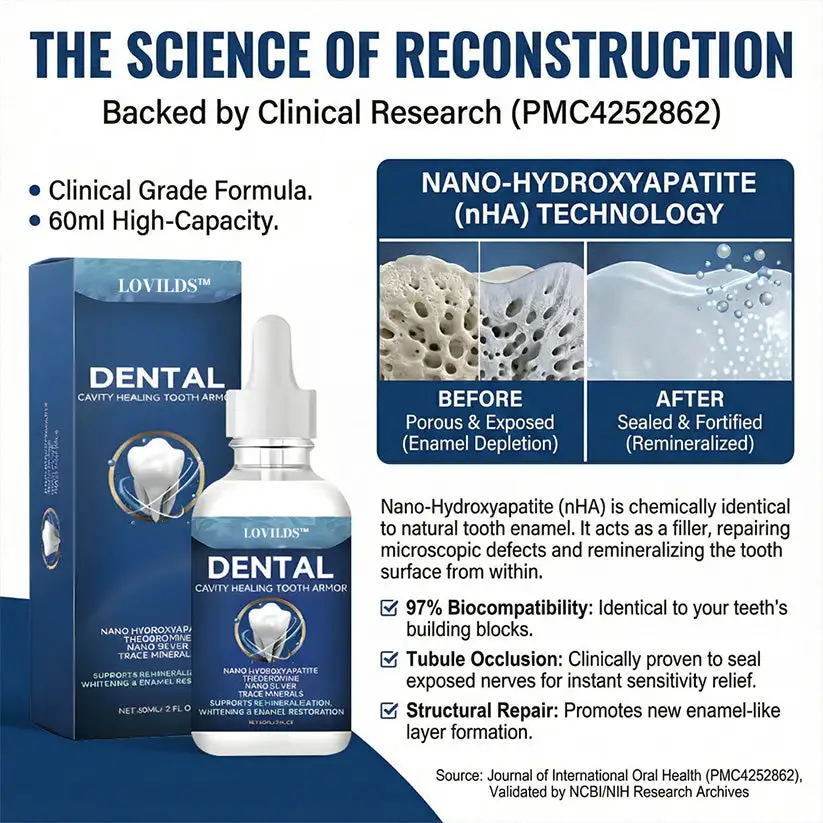

Modern research proves that enamel behaves differently when mineral loss is addressed early—before the pain, before the drilling, and before the damage becomes irreversible.

The question changed from “How do we remove decay?” to: “What if we could replace the minerals enamel is losing before the cavity even forms?”

This shift led scientists to a breakthrough discovery: Nano-Hydroxyapatite. By reducing the tooth’s natural building blocks to a microscopic scale, we can finally “refill” the porous areas of a tooth before they collapse. This is the science that turns the “permanent” process of decay into an interrupted process of repair.